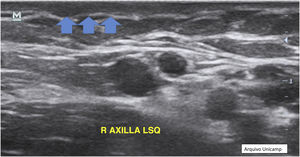

Another possible finding are reactive lymph nodes that have an elliptical well defined shape, with hypoechoic cortical thickening, and an hyperechoic medulla in the central area (Fig. 13).17,23,28 Normally they are 1 cm in diameter and the Doppler assessment shows hilar vessels in the central area or at one of the borders.10,17,25